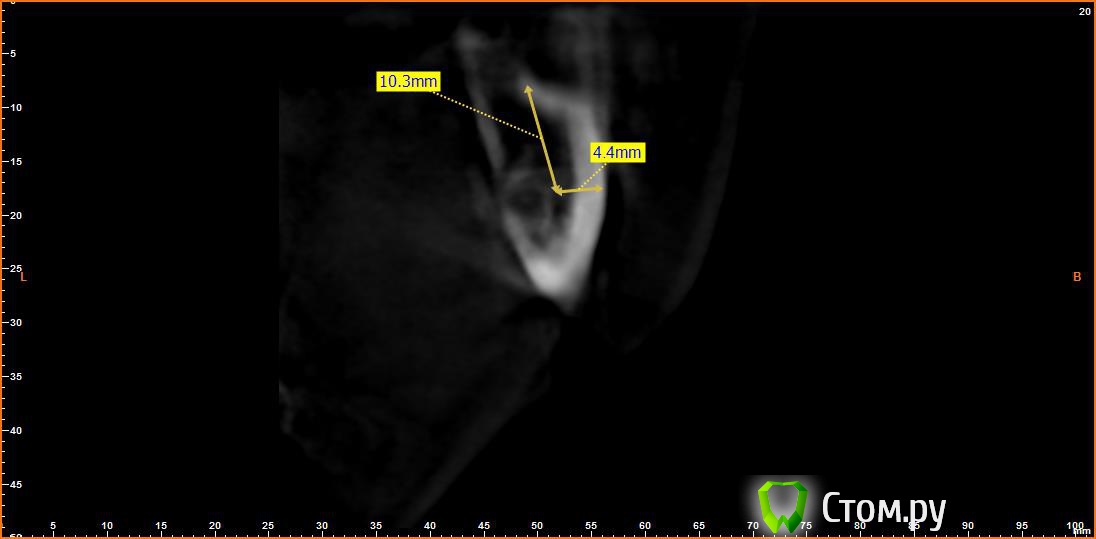

Bier Опубликовано 21 июня, 2014 Поделиться Опубликовано 21 июня, 2014 Выкладываю еще. Пошагово от 34-37темная точка достаточно высоко, это по моему не нерв, нерв ниже, я правильно понимаю? Ссылка на комментарий

Opimar Опубликовано 21 июня, 2014 Автор Поделиться Опубликовано 21 июня, 2014 темная точка достаточно высоко, это по моему не нерв, нерв ниже, я правильно понимаю?Да он ниже и язычнее. Провел от менталиса там еще запас есть. Ссылка на комментарий